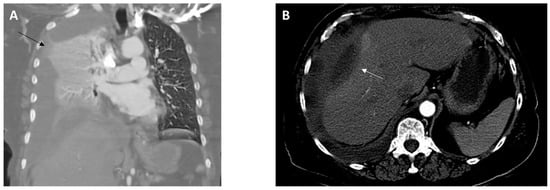

A right perihepatic drain was placed to address the thick-walled collection along the lateral aspect of the right liver lobe, with 35 mL of purulent material collected. The patient received four weeks of piperacillin/tazobactam prior to transitioning to amoxicillin-clavulanate. A CT scan of the abdomen performed at the completion of IV therapy revealed near resolution of the perihepatic abscess and a low-volume residual loculated pleural effusion. The perihepatic drain was removed, and the patient continued amoxicillin/clavulanate to complete a six-month total duration of antimicrobial therapy. A subsequent CT scan of the abdomen showed complete resolution of the perihepatic abscess (Figure 5A) and empyema (Figure 5B).

Figure 5. CT abdomen/pelvis with intravenous contrast obtained four months following hospital discharge shows resolution of the empyema ((A), coronal view) and perihepatic abscess ((B), axial view).